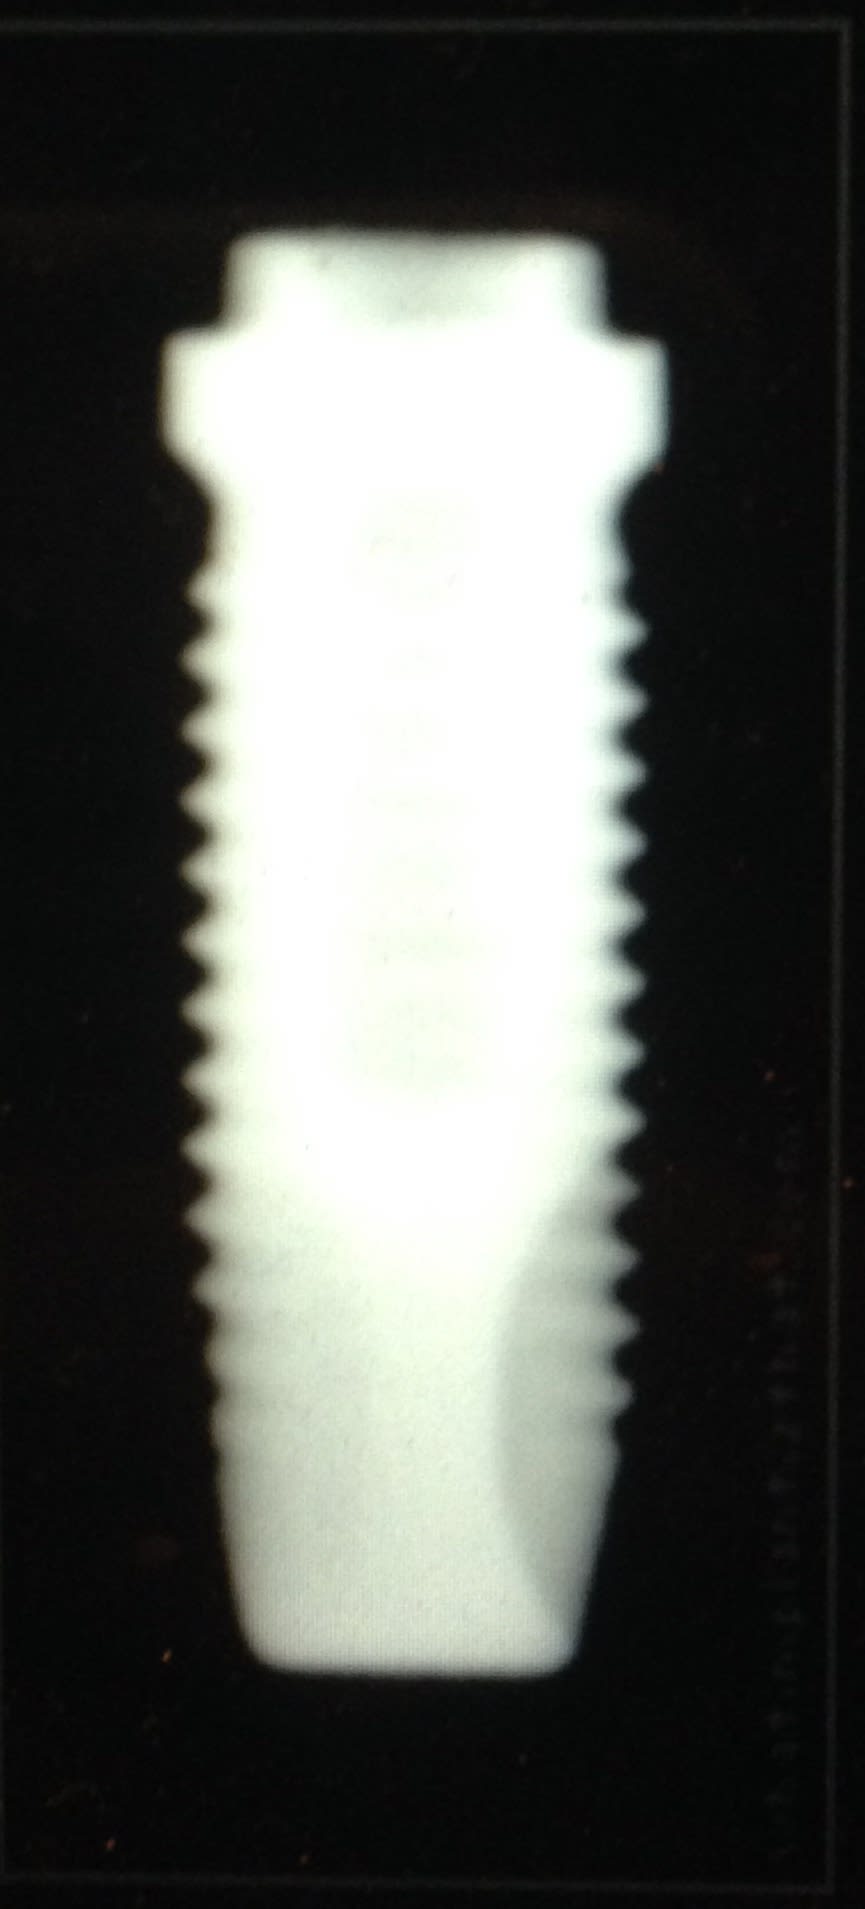

Et Les fameux Implants Branemark l'original , MK1, 2, 3, 4 ..... c'est comme les Peugeot une fois qu'ils ont trouvé Le filon , ils l'exploitent à mort 206 207 208 😊. C'est du business. Mais on remarquera que finalement Adams et d'autres avaient déjà presque tout compris bien avant En ce qui concerne la forme de l'implant et son fonctionnement . Et on se rend compte dans la 2eme moitié du siècle que Le titane supplante les autres métaux. Père de l'implantologie moderne (osseointegration + propriétés mécaniques bien meilleures pour le titane)

Img 1276 mn5sw9 - Eugenol

Img 1277 gmam2f - Eugenol

Img 1278 heox4v - Eugenol

Img 1279 cefubz - Eugenol